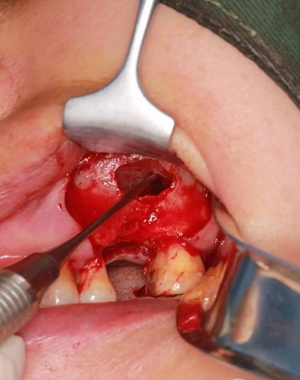

改良式外提升工具盒-外提 科貿(mào)嘉友收錄

六個(gè)月之后